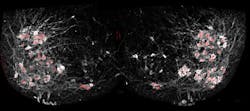

To get around this shortcoming of electrode readings, Samuel Pfaff, a professor in Salk's Gene Expression Laboratory, and his team used a fluorescent sensor protein called GCaMP6f that lights up whenever a neuron is activated. Unlike the electrodes, the protein could easily be added to many different cells at once. When Pfaff and his colleagues added GCaMP6f to motor neurons, they could watch with a microscope which cells were activated in a mouse spinal cord when chemicals that turn on walking circuits were added. What's more, Pfaff says, the method does not require any post-image processing for interpretation, as the signals are raw and able to been seen through a microscope.

Pfaff's group used the new method to answer a long-standing question about how a collection of cells in the spinal cord, called the locomotor central pattern generator (CPG), connects to the right motor neurons to allow movements like walking. The CPG, Pfaff says, is where relatively simple signals from the brain—to walk forward, or move your hand off a hot stove—are translated into more complex instructions for motor neurons to control muscles.

By tweaking the locations and identities of motor neurons, and then watching the resulting patterns of activation using their new fluorescence technique, Chris Hinckley in the Pfaff laboratory found that the CPG didn't rely solely on the cells' locations to connect to them. Instead, the genetic identity of each subtype of cells—what makes those that control the quadriceps muscle different from those that control the calf muscle, for instance—is also important.